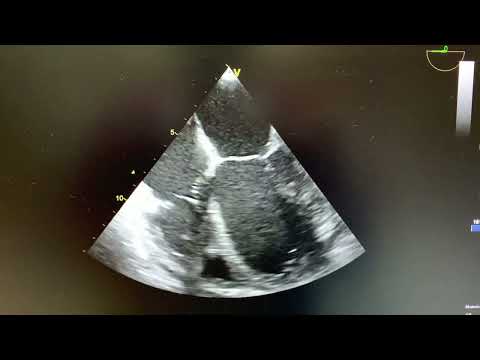

Plano medioesofágico de 4 cámaras a 0º

En la ETE se aprecia VI dilatado con acinesia global y FEVI severamente deprimida, a nivel inferoapical se aprecia masa redondeada de 2.4 cm x 1.8 cm hipoecogénica adherida al endocardio compatible con un trombo, orejuela de la aurícula izquierda libre.

Imágenes del trombo apical del paciente de nuestro caso junto a otros ejemplos de trombos apicales del ventrículo izquierdo.